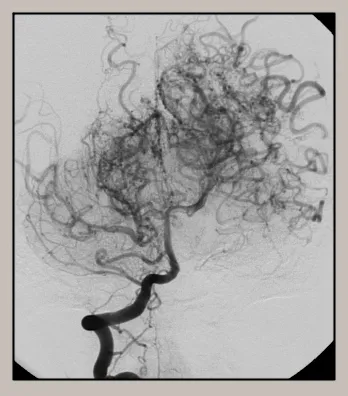

일본에서 처음으로 확인된 모야모야병은 "연기 퍼프"를 뜻하는 일본어 용어에서 그 이름이 유래되었습니다. 이 이름은 뇌의 동맥이 막혔을 때 발생하는 작은 혈관의 모양을 적절하게 묘사합니다. 이러한 측부 혈관은 제한된 혈류를 보상하기 위해 흐릿한 연기 같은 네트워크를 형성합니다. 이 현상은 뇌에 혈액을 공급하는 내경동맥이 좁아지면서 발생합니다.

모야모야병 진단에는 병력 평가, 신체검사, MRI나 CT 스캔과 같은 신경 영상 검사가 결합되는 경우가 많습니다. 이러한 검사를 통해 뇌혈관의 특징적인 "연기 부풀어 오르는" 모양을 밝혀 진단을 확정할 수 있습니다.